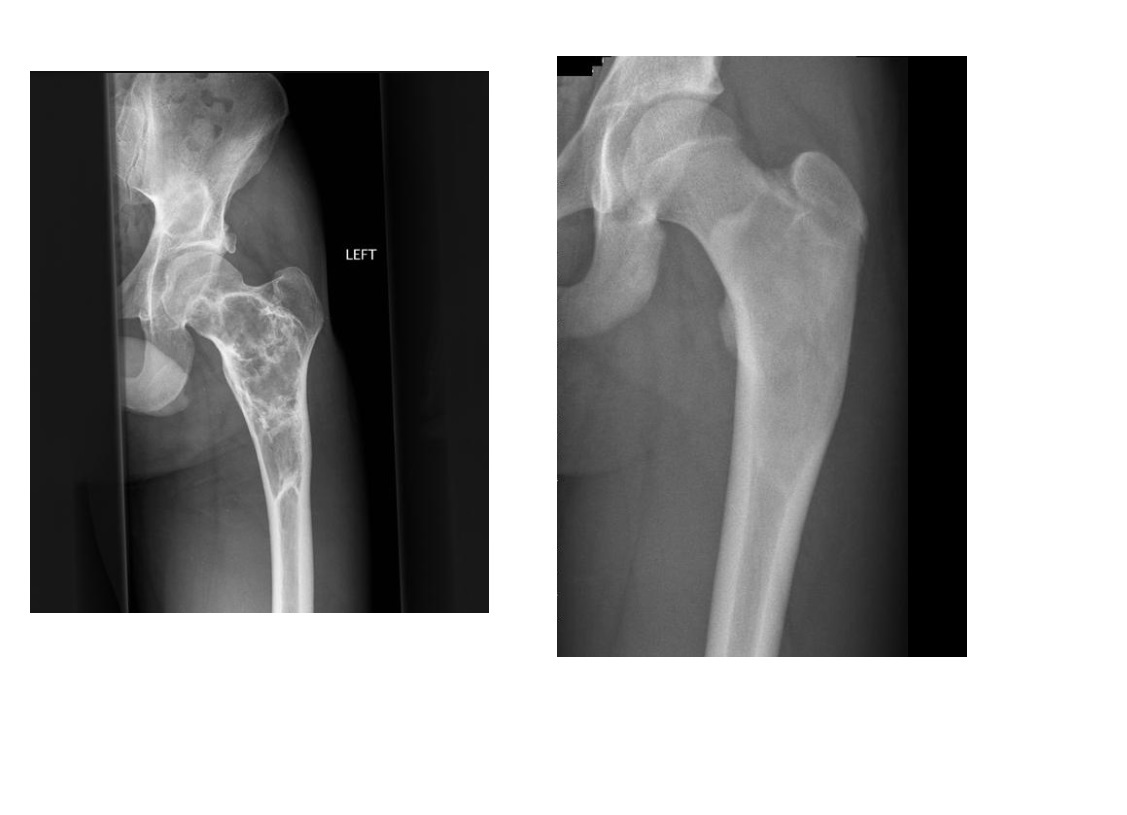

ENCHONDROMA

Commonest location Hands/feet

Long bones: proximal humerus > distal and proximal femur > proximal tibia

Intramedullary and metaphysis

multiple enchondroma

Maffuci - haemangioma

Olliers - multiple enchondroma only

DDx

-Brown tumor (hyperparathyroidism),

-sarcoid - lace like bone lesion phalanges

-intraosseous ganglion

-metastatic disease.

MRI

T1: low to intermediate signal

Fluid-sensitive sequences: lobulated high signal typical of cartilage lesions

Enhancement: peripheral and septal, accentuating lobules

Chondrosarcoma

May be cecondary to

- Osteochondromas

- enchondromas

Chondrosarcomas occur in the pelvis, femur, humerus.

Skull base, TMJ

-Most well differentiated, low grade = ‘low grade chondroid lesion’ , cant differentate from enchondroma

-Bone infarct

Lobular growth

High 2 signal/STIR, low T1

ring and arcs/chondroid matrix islands on CT

Soft tissue extension

**endosteal scalloping. **

if no mineralized matrix/rings and arcs = aggressive/high grade

How to tell chondrosarcoma from enchondroma ?

* Pathological fracture occurring with minimal trauma

* Multilayered or spiculate periosteal reaction

* Permeative or moth-eaten osteolysis

* Cortical destruction

* A soft tissue mass

Endosteal scalloping more than 2/3 cortex